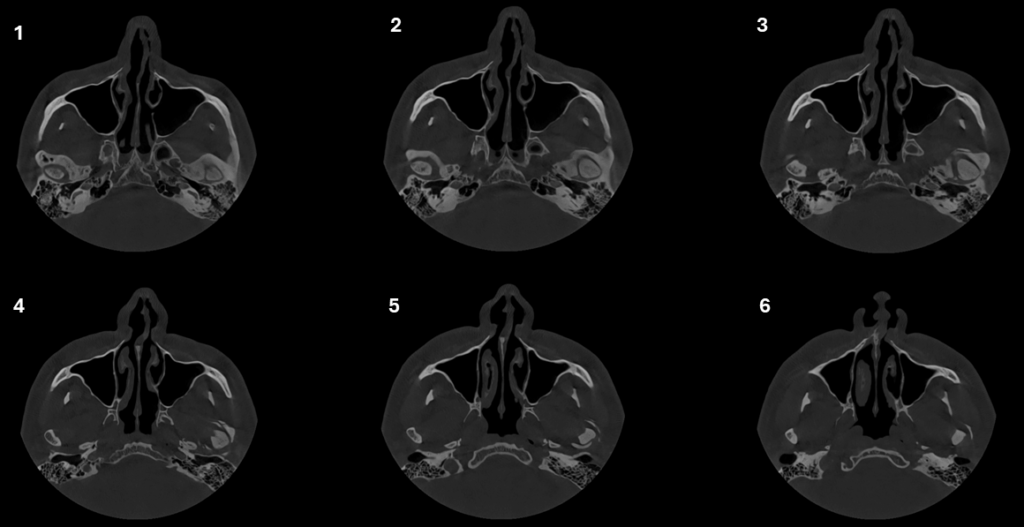

CORTES AXIALES

En la ampliación imagenológica con tomografía computarizada de haz cónico se identifica en el lado derecho se aprecia aplanamiento y esclerosis de la cabeza condilar, con formación de osteofito, presencia de pseudoquiste subcondral y erosión en el contorno superior, además de una disminución del espacio articular en las regiones posterior y lateral. En el lado izquierdo se observa aplanamiento y esclerosis que comprometen la cabeza y el cuello condilar, con osteofito asociado y múltiples cuerpos óseos libres alrededor del cóndilo. Asimismo, se identifica una reducción del espacio articular en las regiones posterior, superior, medial y lateral.